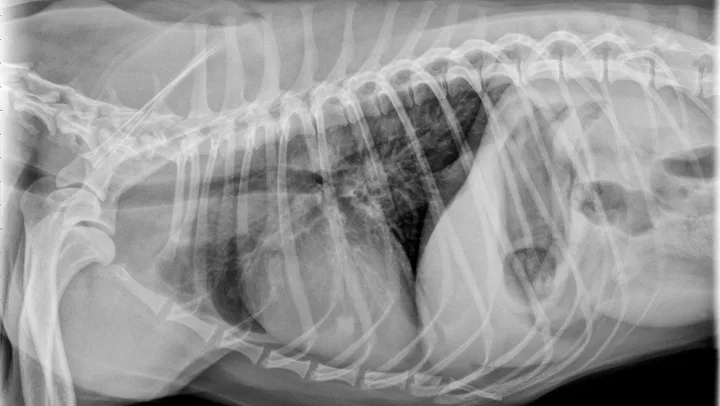

Eosinophilic bronchopneumopathy (EB) is an idiopathic inflammatory hypersensitivity disorder associated with acute onset coughing, gagging, retching, and/or respiratory distress. Radiographs may reveal a diffuse bronchointerstitial pattern or alveolar disease (Figure 3). Patients with EB have airway cytology supportive of eosinophilic inflammation and are negative for parasitic testing.

FIGURE 3

Eosinophilic bronchopneumopathy. Note the heavy, patchy bronchointerstitial pattern.